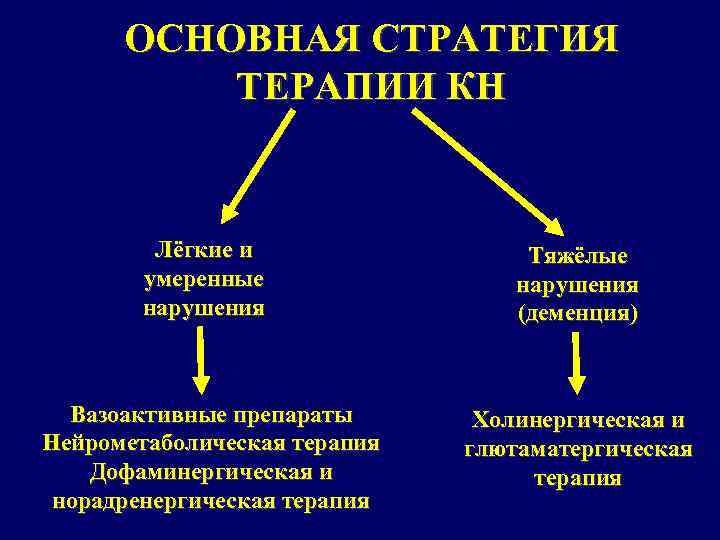

ОСНОВНАЯ СТРАТЕГИЯ ТЕРАПИИ КН Лёгкие и умеренные нарушения Вазоактивные препараты Нейрометаболическая терапия Дофаминергическая и норадренергическая терапия Тяжёлые нарушения (деменция) Холинергическая и глютаматергическая терапия